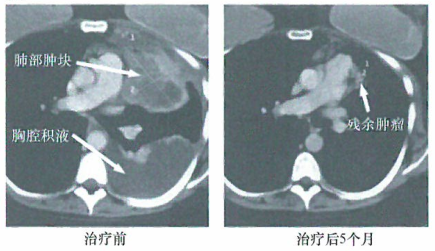

临床上使用称为MDX-010的抗CTLA-4单克隆抗体会在部分患者中产生明显的疗效。海外看病机构爱诺美康介绍,如图所示,黑色素瘤转移的患者作开始免疫治疗(右图)的5个月后,其主要的肺转移瘤和胸膜渗出物(左图)大部分消失,这两幅图是用CT扫描显示的。这个患者首次使用反复注射树突状细胞的方法进行治疗。这种树突状细胞的MHCII受体己在体外与MART-1黑色素瘤抗原寡肽结合负载。

在这一治疗后,再注射抗CTLA-4抗体。这样明显的疗效反映/这种免疫治疗方法的潜能。但由于它只能在很小一部分治疗患者上达到这样的疗效,因此其至今还未被广泛认同。